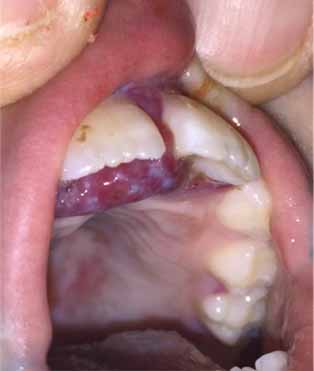

Mouth – Gums with beefy red, hypertrophied excoriations, without drainage.

He was treated with IV vitamin C and had brisk and dramatic improvement in his pain. Resorption of the gum hypertrophy and hemorrhage was rapid. Pain resolved, and he had improved range of motion and use of his wrist. He had continued difficulty walking due to the flexion contractures of his knees.